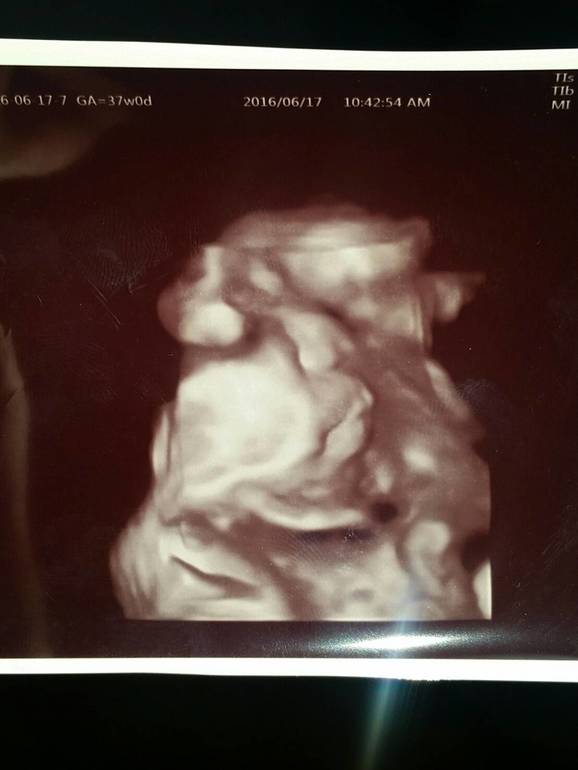

сегодня были в больнице.муж со мной ходил, (последние два месяца у него работы много было,я ходила на приёмы одна). вес у мальша 2800г. я боялась что там уже все 3000,а мне ещё три недели ходить. получается к родам будет около 3400, вроде не крупный. показали нам личико в 4D щеки толстые!нос и рот мужа!моего там и близко не чего нет.так странно смотреть в мoнитор на уже абсолютно сформированного ребёнка и осознавать что это именно он у меня в животе.он мoргал глазками и корчился как новорождённые детки:)